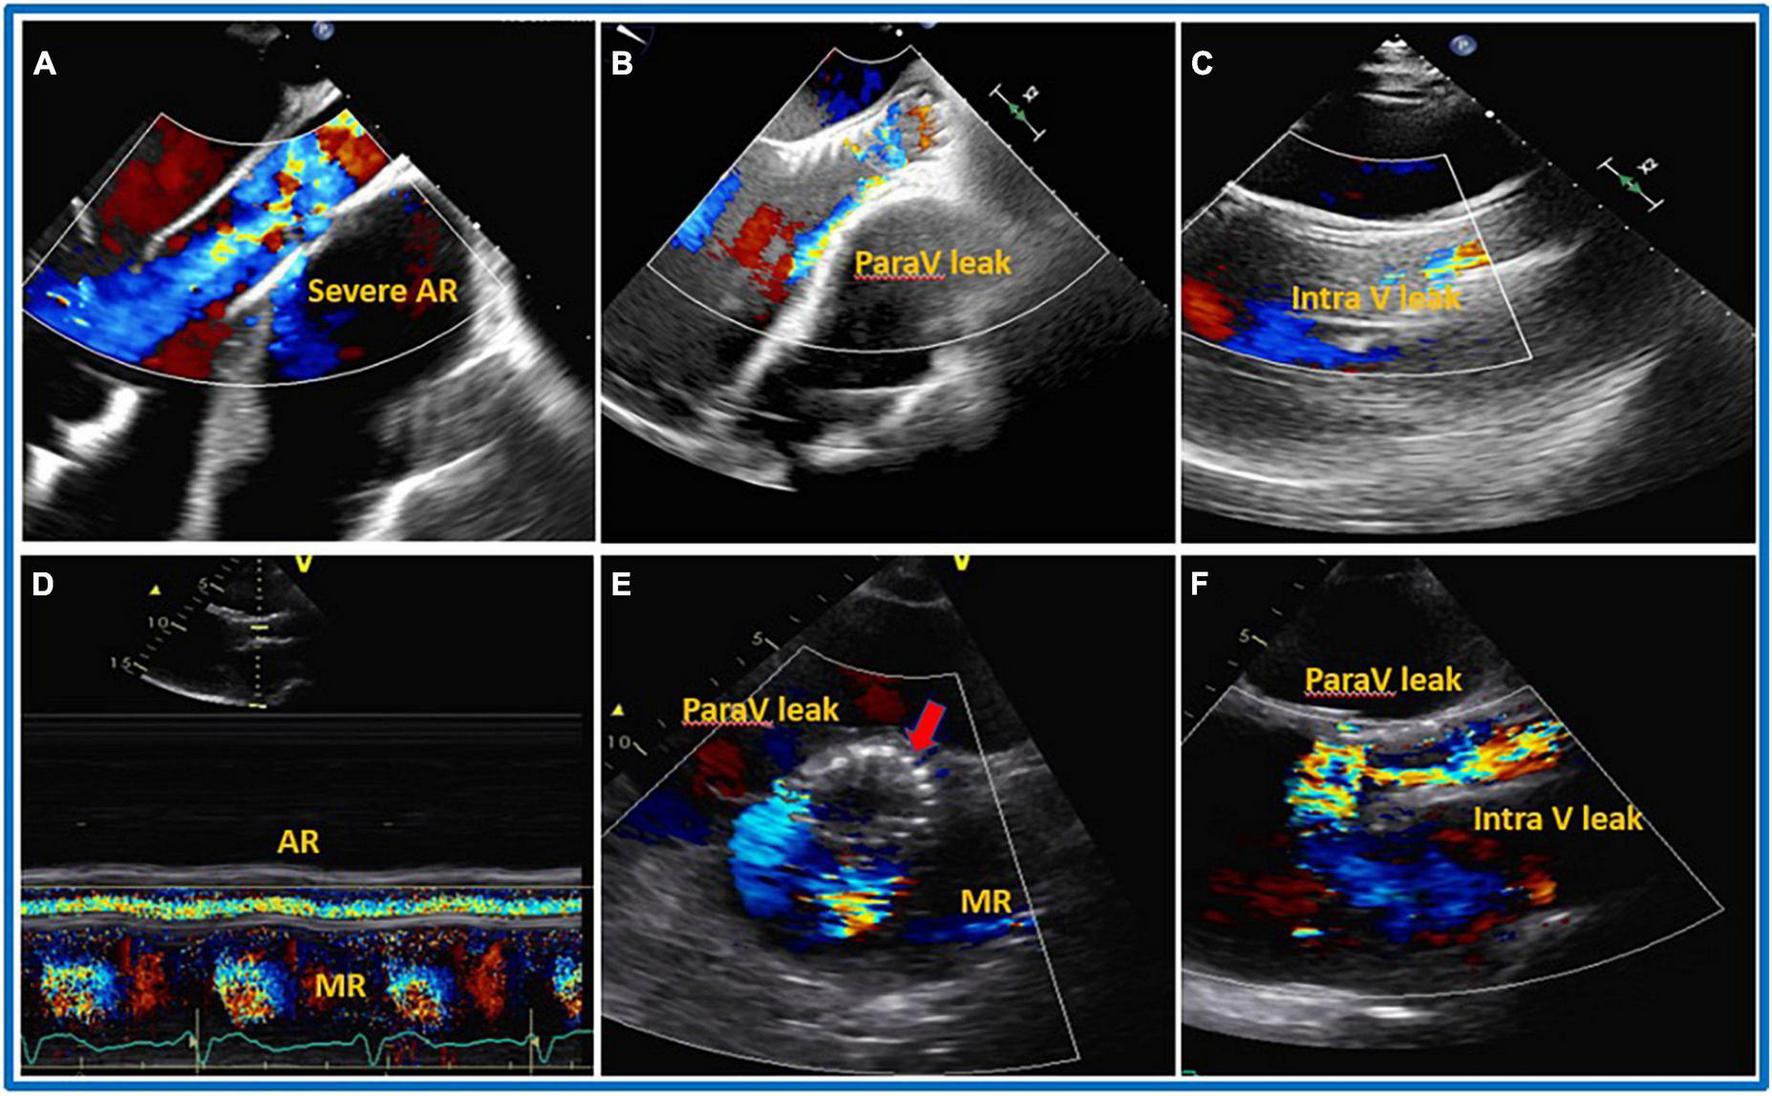

The most common complications associated with TAVI procedures are embolization of the device into the aorta or migration of the prosthesis in the left ventricle (due to the absence of calcium for stabilizing the valve and the vacuum effect of the inflow cannula), as well as the intra-and paravalvular leaks that either occurs after the valve is released or develop during the follow-up period and call for additional intervention (Figure 6). Prior to TAVI, right ventricular dysfunction, dilatation, and pulmonary hypertension—even those that are not clinically evident—must be carefully assessed. Even though there is not enough data in literature, it is required to use medications like milrinone, nitric oxide, and phosphodiesterase inhibitors prior to the procedure along with carefully managing fluid overload during the procedure to lower the risk of RV failure following TAVI. The main causes of periprocedural death are extensive, widespread organ damage and RV failure (kidney, liver) (105). Table 6 summarizes all the different management options with advantages and disadvantages.

FIGURE 6

Transcatheter aortic valve implantation (TAVI) procedure. 32 years old gentleman with severe dilated cardiomyopathy, severe reduced systolic function (Ejection Fraction less than 10%), severe dilated and reduce systolic function of the right ventricle (RV), on left ventricular assist device (LVAD) as Bridge To Therapy (BTT) developed severe aortic regurgitation (AR). On transthoracic (TTE) the patients also had severely dilated RV, severe tricuspid regurgitation (TR) and associated severe liver and kidney dysfunction on hemodialysis. The patient underwent TAVI procedure with mild to moderate residual intravalvular AR. Five days after the procedure, TTE was repeated showing the presence of severe PV leak and the possible protrusion of the prosthesis into left ventricular outflow tract (LVOT). The patient died after 10 days from the procedure due to end stage heart failure and multi organ failure. (A) Pre-TAVI implantation, (B) TTE, mild to moderate paravalvular leak during TAVI procedure and before aortic valve (AV) deployment, (C) parasternal long axis TTE just after deployment, mild to moderate intra and paravalvular leak, (D–F) 5 days later S/P TAVR with likely severe intra and paravalvular leak, possible protrusion of the AV prosthesis into LV. (D) Color M-mode with AR in systole and diastole. (E) Shot axis. (F) Parasternal long axis.